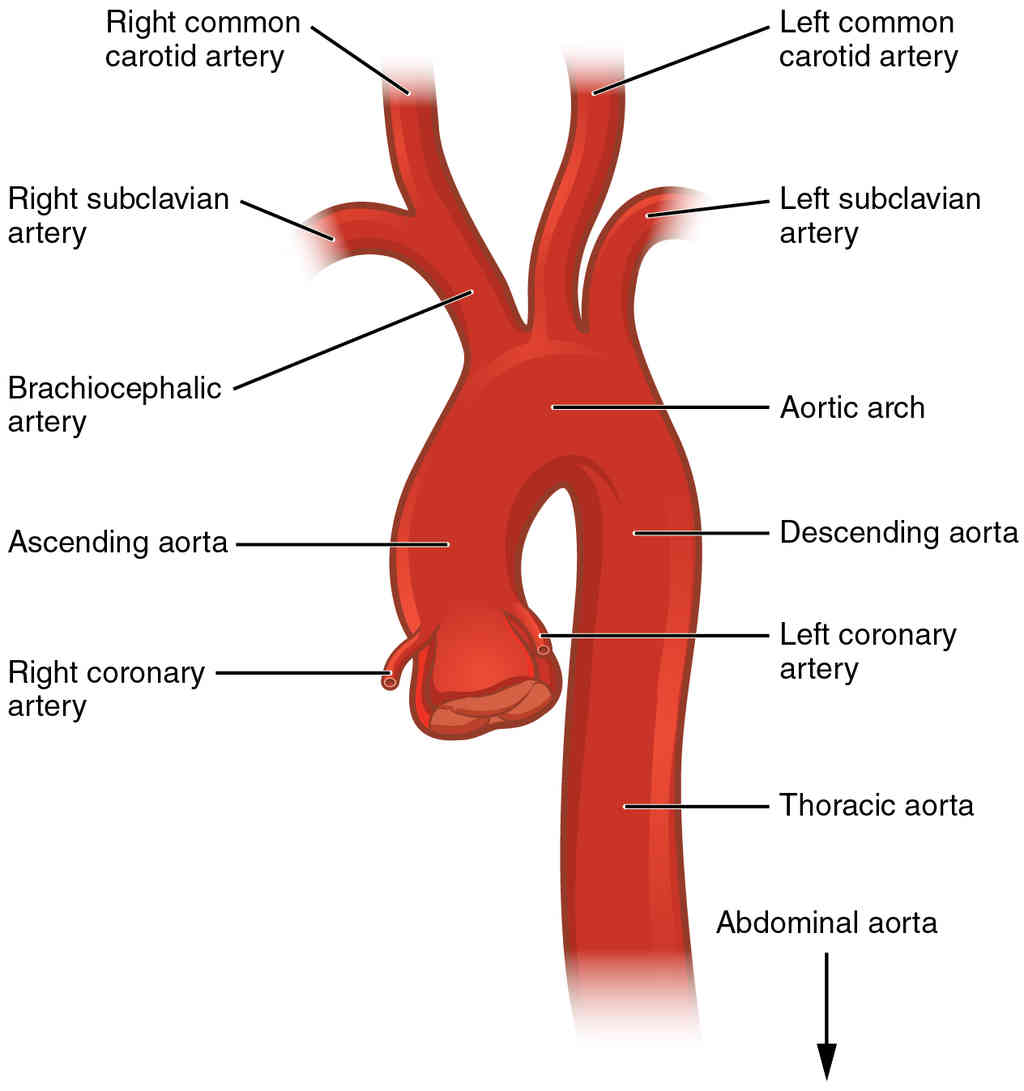

This page is under construction. For now, it is just a resource of the images found in the OpenStax Anatomy and Physiology Handbook. It wil slowly change into a revision tool. Each slide has a number. Use this to refer to the slide. When completed, it will have an unlabelled section, with labelled slides in parallel. On the unlabelled slides, write your answer and use the labelled slide to assess yourself. Keep track by also noting the number on each slide. Improvement at each attempt is important, more so than full marks on a first attempt.